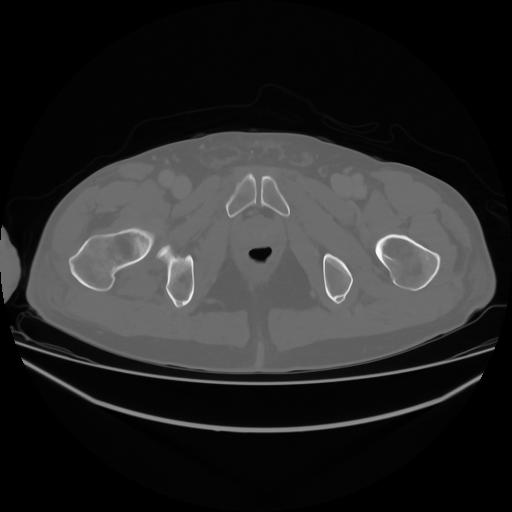

4 CUERPO,CE,Axial,3.0,CUERPO,,